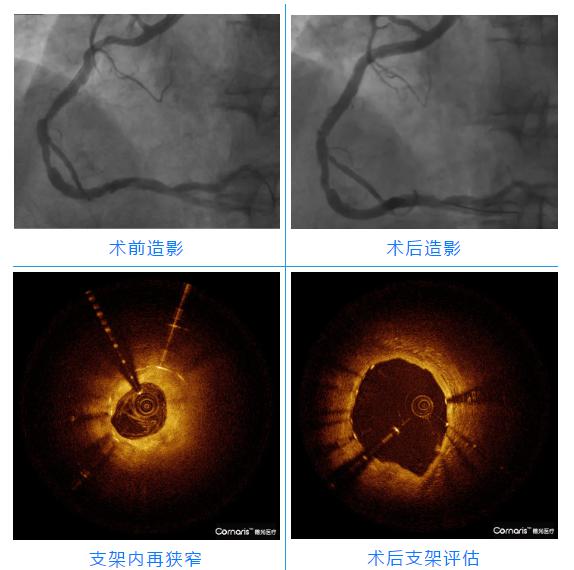

第一例患者是一位59岁的男性,高血压、糖尿病20年,支架术后11年,活动后间断后背疼痛,出汗,心前区疼痛,头蒙4年,再发加重一周入院,行PCI手术治疗,冠脉造影显示右冠支架内再狭窄,狭窄约50%-90%。结合病情与家属充分沟通后,在右冠病变处行OCT检查,显示病变斑块为稳定的纤维脂质斑块,伴有轻微钙化,OCT指导下精准定位及测量,药物球囊在支架再狭窄处释放药物后后,右冠近中段植入双支架,一气呵成,术后复查OCT、造影,支架贴壁、膨胀良好,前向血流TIMI3级,手术结束。